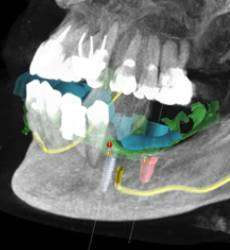

CTARS IPS has a custom made software which can able to guide an implantologist to place an implant in a predetermined surgical plan which will be more precise and accurate to the deep insight about patient anatomy and also helps in reducing the time duration and increasing patient comfort.No two patients teeth are the same. That’s why each and every CTARS IPS guide is custom made to fit your implant plan and patient’s anatomy.CTARS is available with tooth or bone (dentulous or edentulous) supported.

Zygoma Implant Positioning Guide